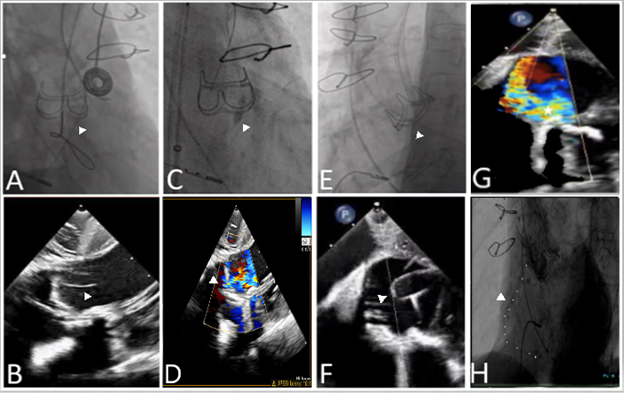

📝 Want to know contemporary & future options for the management of severe 2ndary MR? Check out this new JCF SotA Review to learn about TEER & emerging transcatheter MV repair & replacement devices here! 🔗bit.ly/4fbGuKY